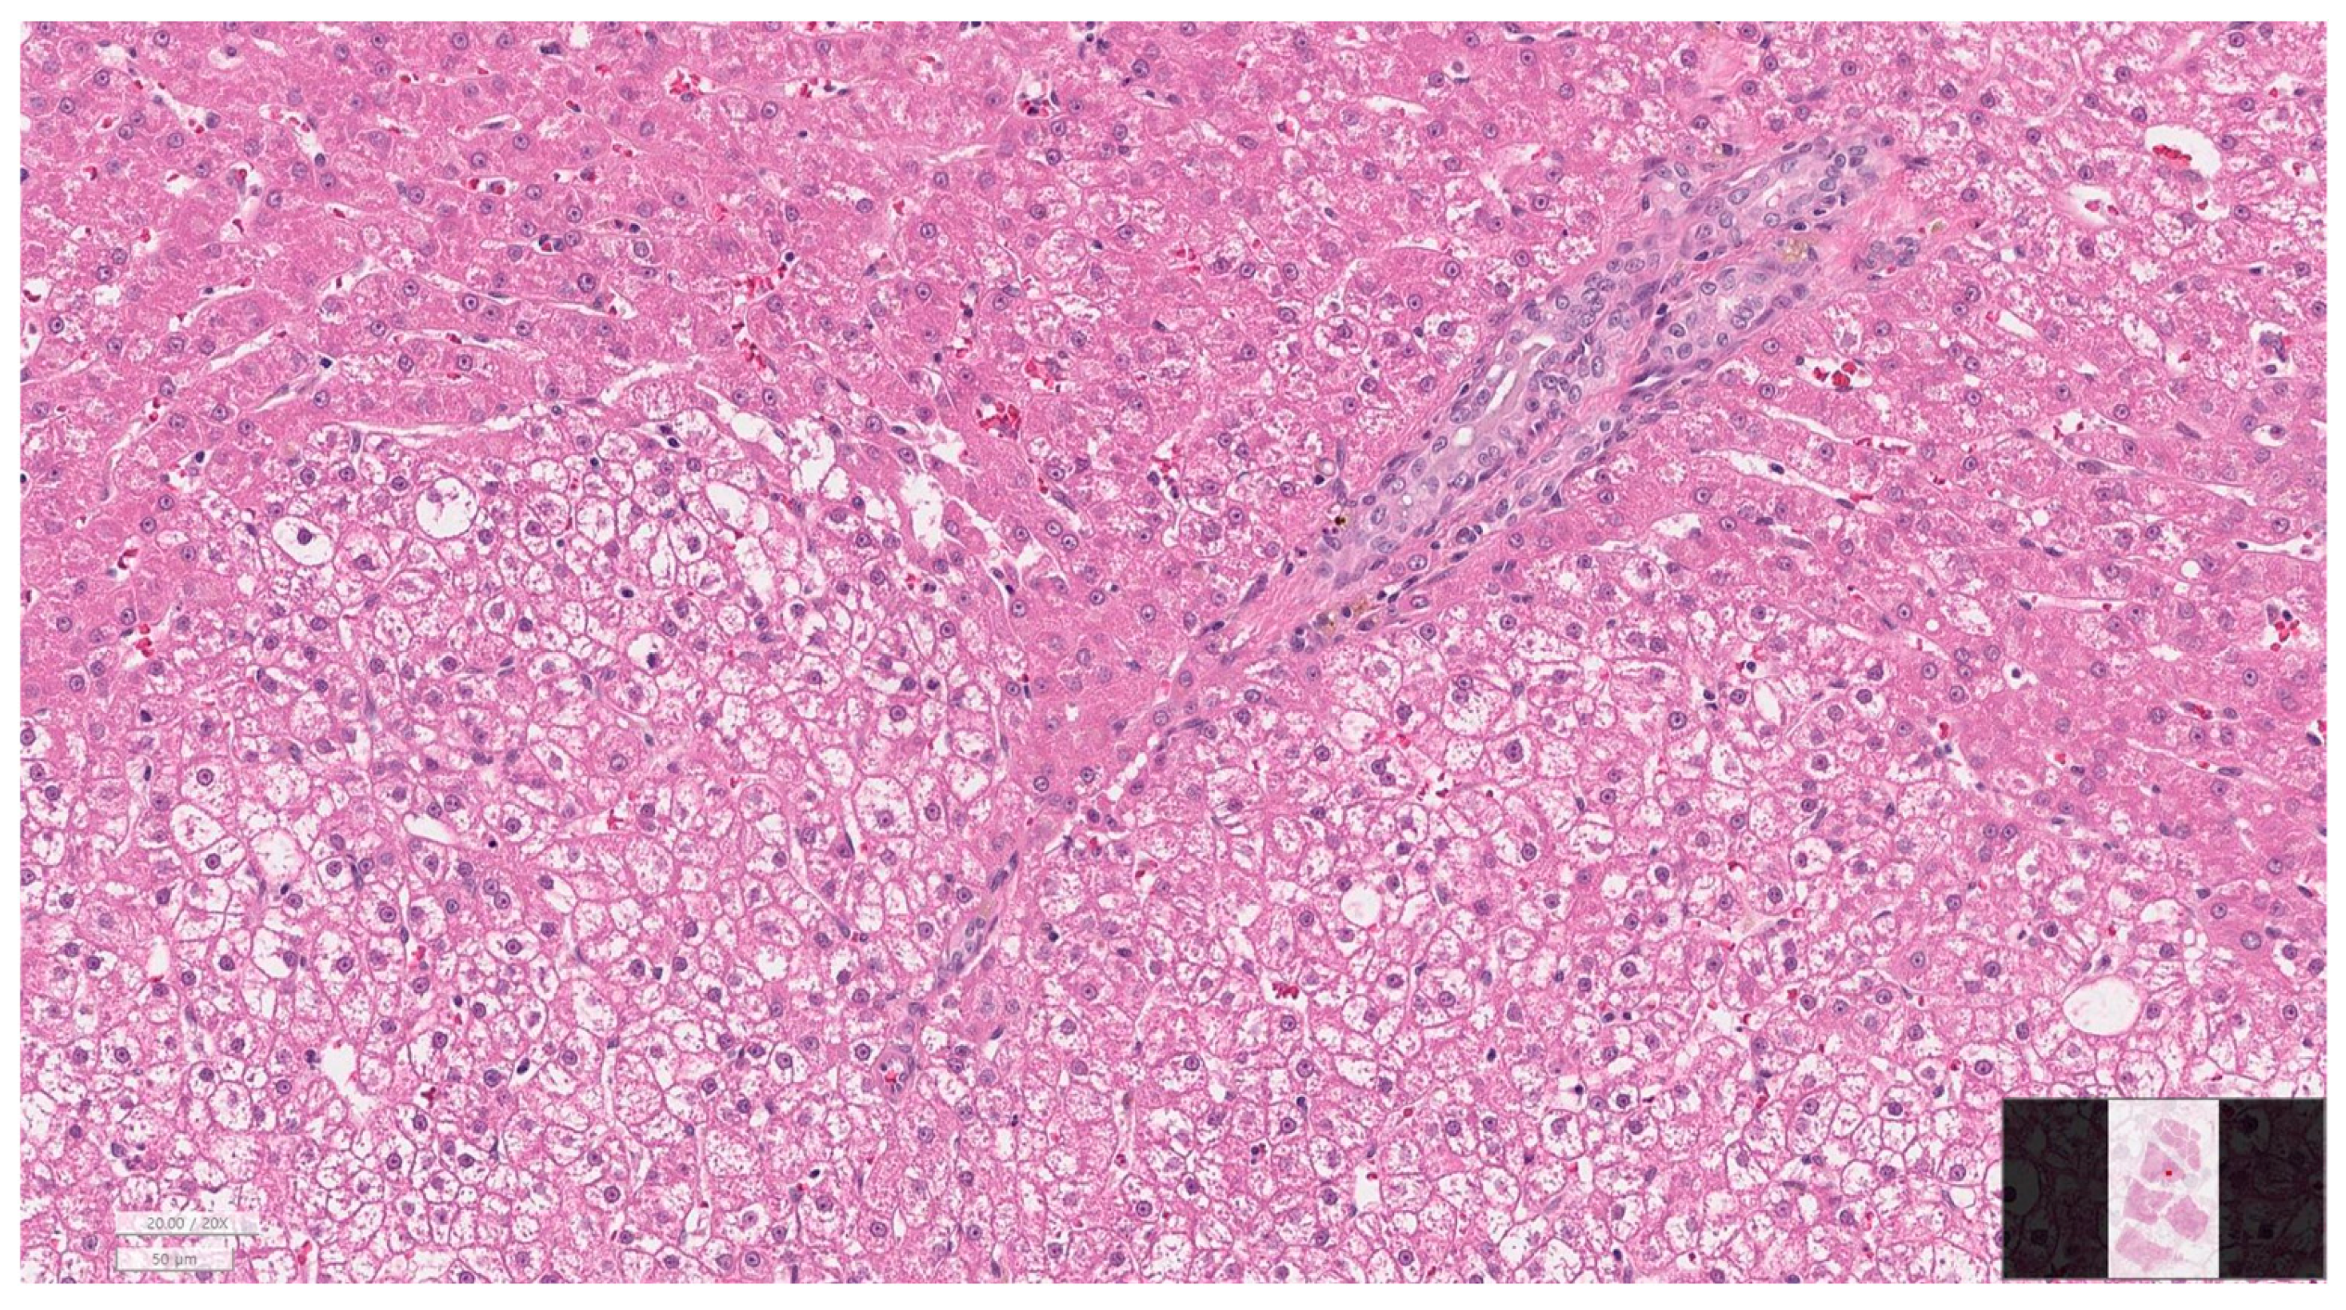

2.7. Histopathological Evaluation

3.6. Histopathology of Gallbladder and Liver

| Hepatitis grade | None | 8 (38.1) |

| Mild | 3 (14.3) | |

| Moderate | 7 (33.3) | |

| Severe | 3 (14.3) | |

| Cholangiopathy grade | None | 8 (38.1) |

| Mild | 6 (28.6) | |

| Fibrosis stage | None | 9 (42.9) |

| Moderate | 5 (23.8) | |

| Severe | 4 (19.0) |